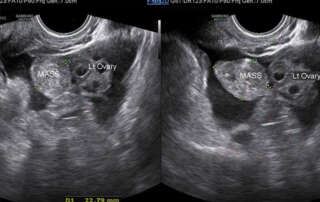

Funneling of the urethra in Valsalva (Article 1) and a phrenic (Diaphragm) endometriosis

vNOTES hysterectomy technique in a case with big broad ligament fibroid: Video Article